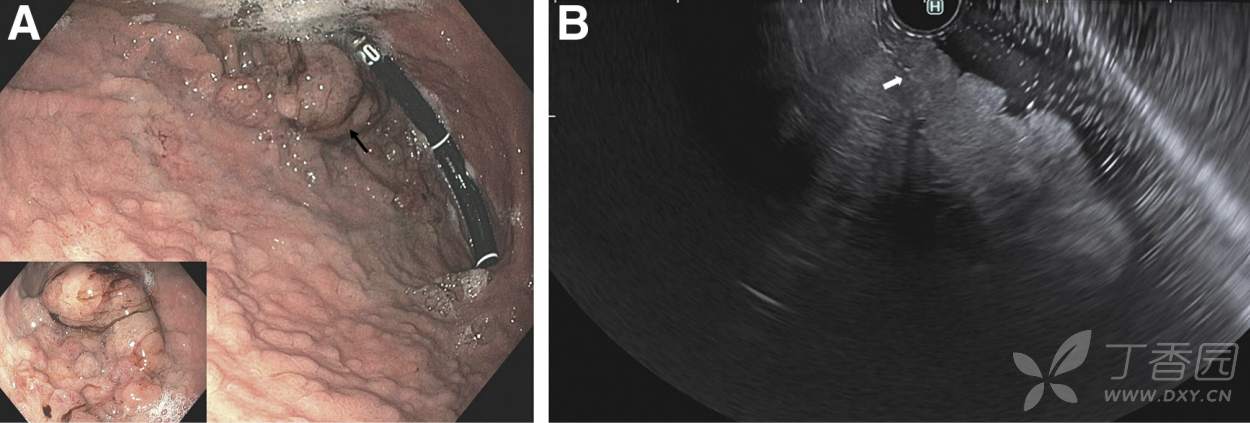

胃镜提示:胃底胃体遍布大小不一的“息肉”样病变(图A),超声胃镜提示病灶呈低回声的粘膜层非环周性肿块(图B)。